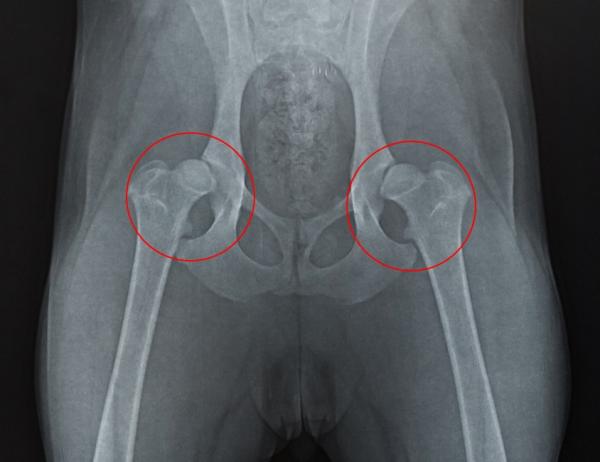

• Displasia de cadera: esta es una malformación congénita que se produce cuando la articulación que une el fémur no encaja con el hueso de la pelvis. Sucede durante el crecimiento del animal, donde la cadera se va desplazando hacia los laterales impidiendo que el perro se mueva de manera adecuada y se vuelve más grave con el tiempo. A pesar de ser bastantes los perros que sufren este problema, en la mayoría de casos no llega a desarrollarse hasta el final, pero si lo hace notaras que tu mascota cojea y sufre dolor al realizar actividades tales como correr, sentarse o subir la escalera.

Dependiendo de la causa que esté produciendo dolor de cadera a tu perro se puede tratar de forma médica, con o sin cirugía. Se recomienda acudir al veterinario si observas algún síntoma descrito anteriormente para que realice una radiografía y detecte cuanto antes el problema, sobre todo si se trata de displasia de cadera, ya que cuando antes se detecte, más fácil y rápido será su tratamiento y mejora. Así, estos son los tratamientos para el dolor de cadera en perro según su causa, aunque no son los únicos y siempre será el veterinario quien indique cuál es la mejor opción para cada paciente:

• Displasia de cadera: en este caso no existe cura definitiva, pero existen tratamientos apropiados para aliviar el dolor y dar una mejor calidad de vida a tu peludo. Si la displasia no está muy avanzada o por alguna razón no se puede operar al perro se aconseja restringir cualquier ejercicio, evitar el sobrepeso o en caso de que ya lo padezca, el veterinario te dará una dieta estricta a seguir para que baje de peso. Normalmente, también se combina con hidroterapia o masajes para aliviar el dolor de las articulaciones. Los perros con este problema suele necesitar la administración de antiinflamatorios, analgésicos y medicamentos para proteger los cartílagos o condroprotectores. Hay que tener en cuenta que el tratamiento sin cirugía tiene que llevarse a cabo durante toda la vida y no elimina la displasia, sino que impide que se empeore y alivia el dolor, aunque la mayoría de veces es suficiente para que tu perro tenga la calidad de vida que se merece. Si el tratamiento médico sin cirugía no da resultados o la displasia está muy avanzada, se va a requerir una cirugía donde después de esta no habrá que mantener un tratamiento durante toda la vida. Existen diferentes técnicas quirúrgicas para solucionar este problema, pero será el veterinario el que elija cuál será mejor para tu perro después de un diagnostico apropiado. En este otro artículo de unCOMO te explicamos Cómo cuidar a un perro con displasia de cadera.